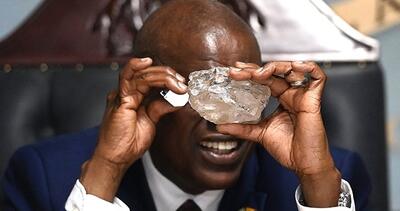

اشعه ایکس

به لطف یک کشف تصادفی، دانشمندان از یک منبع ستارهای کاملا جدید از انفجار تابش اشعه ایکس آگاه شدهاند.

اسکن اشعه ایکس به معمای چگونگی قرار گرفتن تابوت بدون دریچه لیدی چنت پاسخ میدهد.

سامسونگ به دلیل عدم رعایت استانداردها و قرار گرفتن ۲ کارمند در معرض اشعه ایکس کمتر از ۸ هزار دلار جریمه شد.

شرکت سامسونگ به دلیل عدم رعایت استانداردها ۸ هزار دلار جریمه شد.

کشف بزرگترین الماس قرن با اشعه ایکس! - تکناک

شرکت کانادایی Lucara Diamond با استفاده از فناوری انتقال اشعه ایکس، دومین الماس بزرگ جهان را در بوتسوانا کشف کرده است.

اشعه ایکس با دوز پایین میتواند سلولهای تومور مغزی را نابود کند!

پروفسور Pu Kanyi نویسنده ارشد و همکار این مطالعه گفت: «ما از دوزهای بسیار پایین اشعه ایکس و MRAPهای کشنده سرطان استفاده کردیم.